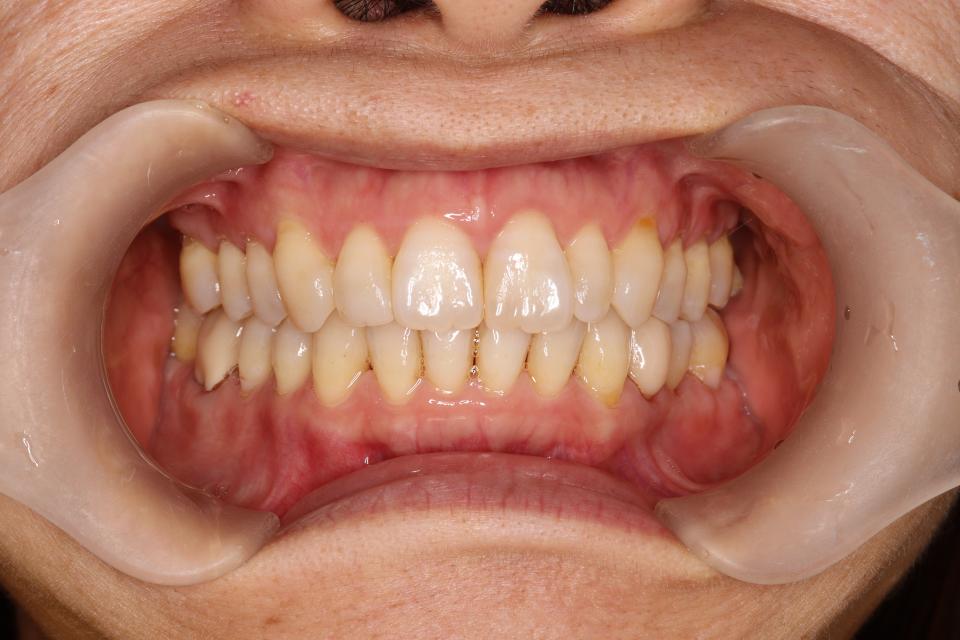

矯正治療後

マウスピース型の矯正治療装置を使用し、歯のやすり掛け(IPR)を行いました。

現在はマウスピース型のリテーナーでで後戻りの防止をして定期的にチェックをしています。

| 矯正治療期間 | 2年9か月 |

| 抜歯の有無 | なし |

| 治療費 | 1,005,000円(検査/診断/施術料) |